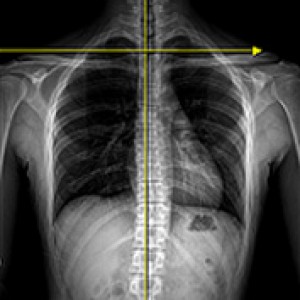

엑스레이 검사

좌우 골반 수평 및 비틀림 측정

흉추, 요추 만곡, 척추 휘어짐 측정

좌우 다리 길이와 틀어짐 측정

엉덩이 관절의 염전각 측정

경골의 회전과 내반 측정